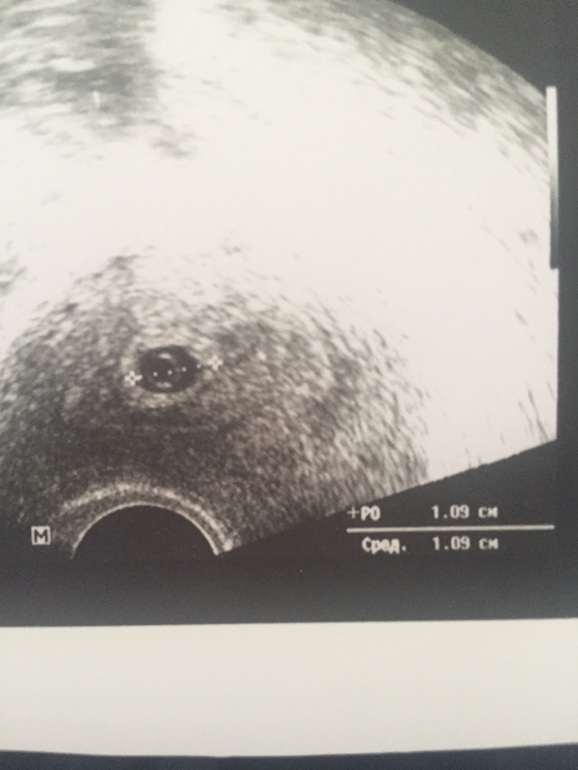

Малыш в матке, представляете?)

Лен, ты как знала)у меня выделения прям кусками коричневыми были, понеслась на узи с утра, все хорошо, растет малыш🙏, ттт.

у меня сб было видно на 7 неделе уже. 160 ударов, хотя ктр был всего 6 мм.

а через неделю ктр уже 18 мм и сб 176

так что растет ого-го.

Вот смотри)